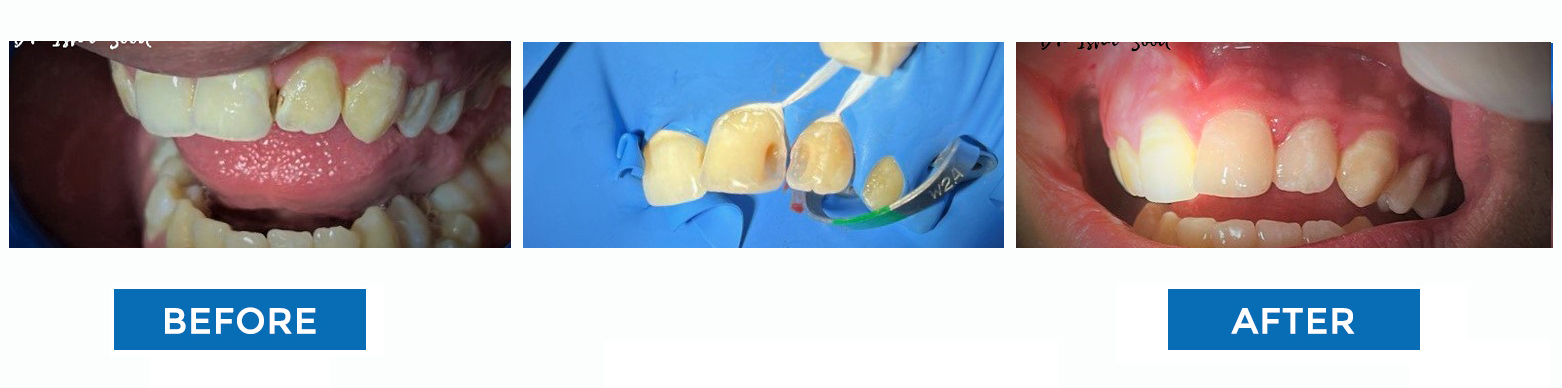

Tooth Coloured Filling (Restoration)

Broken Tooth Repaired with Tooth Coloured Filling

Discoloured Fillings Changed to Tooth Coloured

Aesthetic Filling